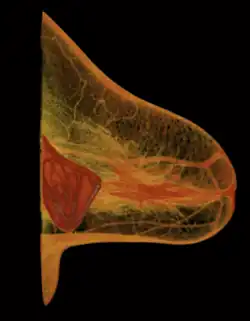

A breast implant is a prosthesis used to change the size, shape, and contour of a person's breast. In reconstructive plastic surgery, breast implants can be placed to restore a natural looking breast following a mastectomy, to correct congenital defects and deformities of the chest wall or, cosmetically, to enlarge the appearance of the breast through breast augmentation surgery.

In surgical practice, for the reconstruction of a breast, the tissue expander device is a temporary breast prosthesis used to form and establish an implant pocket for the future permanent breast implant. For the correction of male breast defects and deformities, the pectoral implant is the breast prosthesis used for the reconstruction and the aesthetic repair of a man's chest wall (see: gynecomastia and mastopexy).